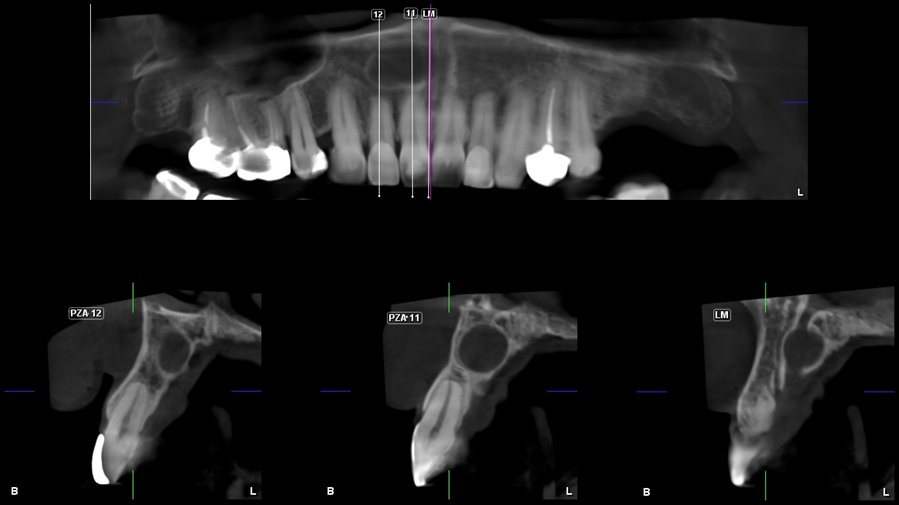

En la radiografía panorámica (Figura 1), se aprecia imagen radiolucida unilocular proyectada sobre zona anterior del maxilar superior, de limites definidos, bordes corticalizados.

A la evaluación de la tomografía volumétrica (CBCT) en los cortes axiales (Figura 2) y transaxiales (Figura 3), se evidencia imagen hipodensa localizada hacia distal del conducto nasopalatino, de limites definidos, borde parcialmente corticalizados, que se extiende en sentido mesio distal de distal de pieza 12 hasta línea media, comprometiendo cortical de conducto nasopalatino.